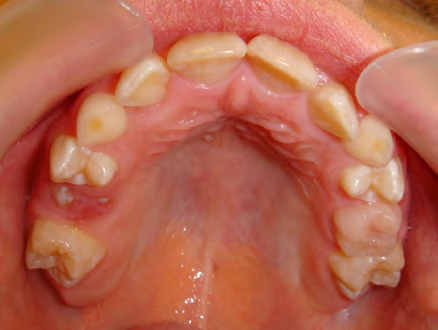

The patient below had severe crowding of both upper canines and the lower right 5. The upper 4’s and 2’s were actually in contact.